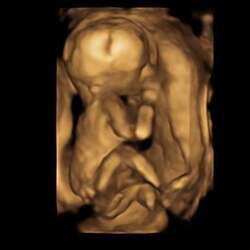

Dit was de 20 weken echo van mijn zoontje. Als ik dat vergelijk met die van jou dan zie ik bij jou toch geen jongen hoor..

Dit is de echo van onze dochter en jou echo vind ik hier meer op lijken. Deze echo is gemaakt met 14+3 weken

Dit was bij ons met 15 wkn. (Jongen)

Ieder bedankt voor de reactie! Had stiekem gehoopt dat iemand kon zeggen: “hè, zo zag mijn jochie er ook uit” Hahah. 3D echo is volgende week gepland mochten jullie het leuk vinden zal ik hier de uitkomt met wat foto’s plaatsen. Vind het erg spannend nu, ergens denk ik. De Nub (die volgens experts heel overtuigend was) mevrouw van de pretecho en de Vk kunnen er toch niet alle 3 naast zitten 😅 Maarja de foto is wel gek inderdaad en de VK was zelf niet overtuigd, mevrouw van de pretecho weer wel.